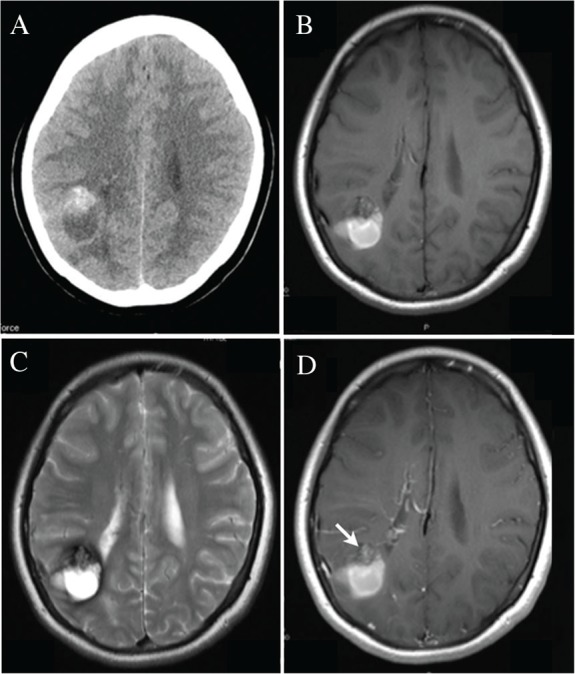

15岁女孩,既往有哮喘和过敏性鼻炎病史,主诉右侧颞区间歇性头痛,持续时间为身体运动后5 min。一个月后,她经历了严重的头痛,随后视力模糊,并被转介到以前的医院。她被诊断为右顶叶颅内出血,被转移到我们医院。入院时的神经系统检查没有发现明确的异常。入院后她的症状逐渐好转。平片电脑断层扫描显示在右顶叶有一个高密度肿块和一个低密度病灶(图1A)。T1加权和T2加权磁共振成像(MRI)均显示一个混合强度肿块,伴有亚急性期血肿,位于右侧壁白质,靠近侧脑室。质量部分增强。未观察到其他损伤(图1B-1D)。她被诊断为海绵状血管瘤伴有亚急性期血肿。

图1,术前CT和MRI表现。(一)平片扫描显示右侧顶叶深部有一高密度肿块和低密度囊肿。在T1- (B)和T2加权磁共振成像(C)上,肿块显示混合信号强度。邻近囊性病变在T1- (B)和T2加权磁共振成像(C)上均显示高信号强度,提示血肿处于亚急性期。钆增强T1加权磁共振成像显示混合信号强度肿块部分增强(箭头)。